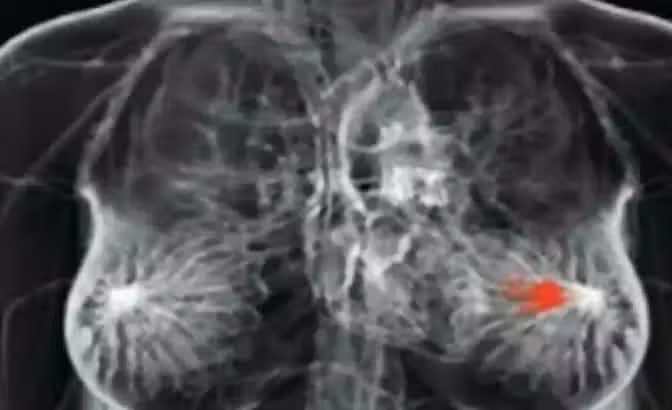

身體發生「4狀況」是「乳癌」前兆!別再只靠手摸「胸部腫塊」測腫瘤 女性朋友一定要知道!

如果你還認為在乳房中發現了一個局部疼痛的獨立腫塊,就是乳房發生癌症的跡象的話,那你可能就錯了!事實上,乳癌出現的腫塊其實都是分散在乳房的各處,像是種子一般的,甚至在某些情況很多乳癌患者是根本沒有腫塊的。